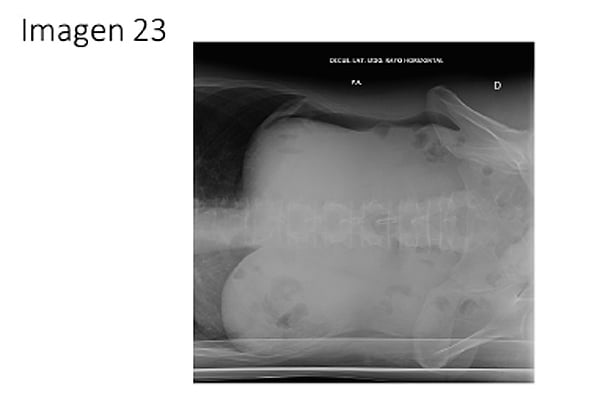

23. Paciente de 53 años sin antecedentes de interés que acude a urgencias por epigastralgia intensa que irradia difusamente al resto del abdomen. Había consultado en urgencias 3 días antes y se le dio el alta con paracetamol que fue efectivo. Reacude ahora por persistencia del dolor con sensación distérmica, náuseas y vómitos que condicionan la ingesta oral. En la exploración tiene un abdomen duro con dolor difuso que mejora con la flexión ventral del tronco. Se le realiza una radiografía de abdomen en la que se observa lo que muestra la imagen IMAGEN (23) ¿Cuál es la principal sospecha diagnóstica?:

-

Obstrucción de intestino grueso.

Perforación gástrica.

Suboclusión de intestino delgado.

Íleo adinámico.